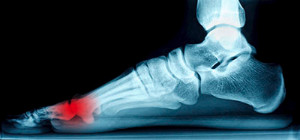

Heels spurs are often defined as a buildup of calcium deposits that form on the underside of the heel bone. When the foot muscles or ligaments are inflamed or strained, a heel spur may develop. Heel spurs can be particularly painful when partaking in activities such as walking, running, or jogging. To help care for a heel spur, it’s suggested that the affected foot is regularly rested and iced. Performing stretches before getting out of bed, wearing properly fitted shoes as well as inserts, and maintaining a healthy weight, can all benefit in relieving the discomfort of a heel spur. In order to treat this condition, it’s suggested you seek the professional care of a podiatrist.

Heel spurs are formed by calcium deposits on the back of the foot where the heel is. This can also be caused by small fragments of bone breaking off one section of the foot, attaching onto the back of the foot. Heel spurs can also be bone growth on the back of the foot and may grow in the direction of the arch of the foot.

Older individuals usually suffer from heel spurs and pain sometimes intensifies with age. One of the main condition's spurs are related to is plantar fasciitis.

Pain

The pain associated with spurs is often because of weight placed on the feet. When someone is walking, their entire weight is concentrated on the feet. Bone spurs then have the tendency to affect other bones and tissues around the foot. As the pain continues, the feet will become tender and sensitive over time.